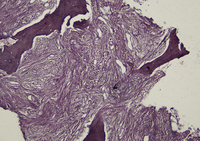

Nucleated Red Blo...